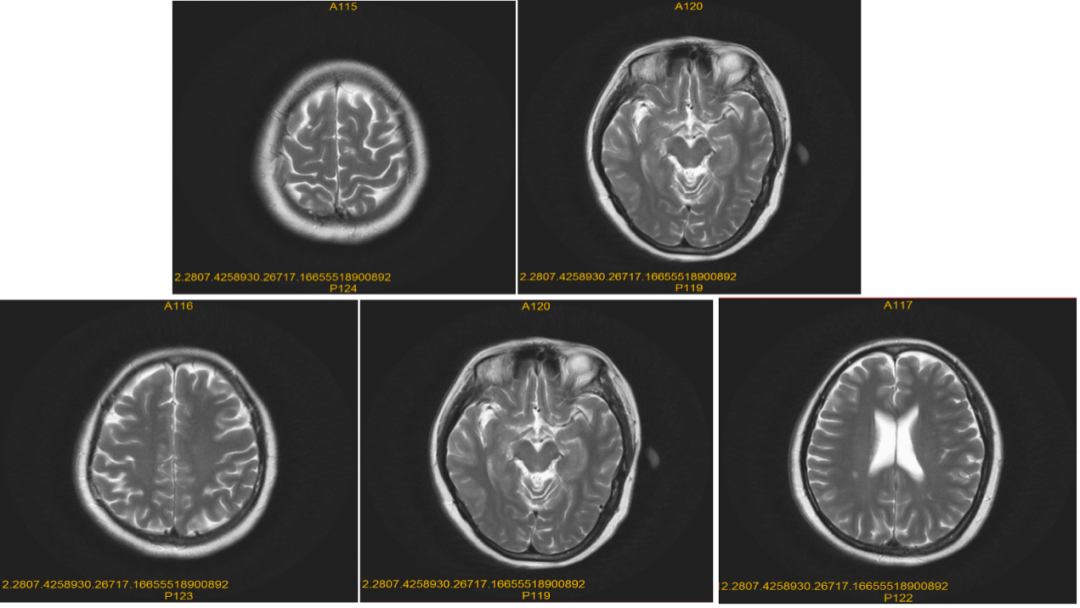

导言 在前两季的病例说栏目中,美宝整理了20例阿美替尼一、二线治疗的经典病例,并邀请相应的研究中心PI进行诊疗点评,以期为临床用药提供指导。本季度病例说仍初心不改,继续对临床中的真实病例进行深层次、多方面地解析,帮助更多临床医生全面了解阿美替尼,为更多患者带来更优治疗方案。 高波 深圳市第二人民医院呼吸内科 副主任医师 中国中药协会呼吸病药物研究专业委员会青年委员会委员 广东省医师协会呼吸科医师分会第四届委员会感染与重症专业组成员 广东省胸部疾病学会弥漫性实质性肺疾病多学科诊疗专业委员会委员 广东省医疗行业协会呼吸病管理协会常委 广东省预防医学会呼吸病预防与控制专业委员会第一届委员会青年委员会委员 深圳市抗癌协会肺结节专业委员会常委 深圳市抗癌协会胸部肿瘤MDT委员会常务委员 深圳市医师协会呼吸内科医师分会第二届理事会肺癌学组委员 深圳市中西医结合学会呼吸病专业委员会委员 深圳市医学会第一届睡眠医学专业委员会青年委员 深圳市健康管理协会第一届呼吸专业委员会委员 病史介绍 辅助检查 图2:颅脑MRI检查 2021.09全身骨扫描:左侧股骨上段骨盐代谢异常活跃,左侧坐骨骨盐代谢稍活跃,考虑恶性肿瘤骨转移可能性大。 2021.09 病理补充诊断:刷检见异型上皮细胞,考虑腺癌。左上叶舌段,活检符合肺浸润性腺癌。 图3:病理检查 病理诊断 病例简介

脑转移病灶:一线阿美替尼联合化疗治疗颅内病灶,第二次疗效评估即治疗5个月(20220308)后疗效评价为PR,治疗12个月后(20221011)患者脑转移病灶疗效仍为PR。

图5:治疗5个月颅脑MRI检查

图6:治疗约12个月颅脑MRI检查